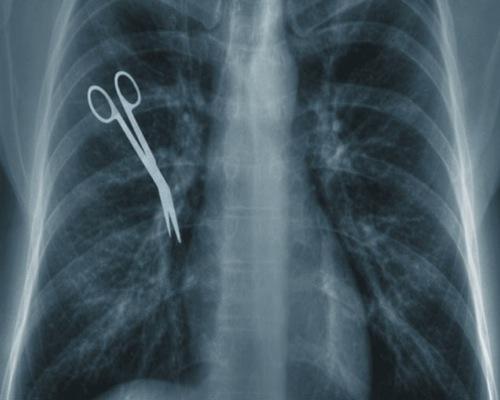

Common medical errors include: misdiagnosis, pharmaceutical (medication, prescription) errors, surgical mistakes, anesthesia errors, emergency room errors, radiology errors (failure to read or properly interpret X-rays, MRIs, cat scans, etc.) and failure to properly diagnose or treat cancer.

In New York, medical malpractice lawsuits must be brought within two and a half years from the time of the malpractice, or within two and a half years from the date of the last continuous treatment for the condition that gave rise to the injury. However, there are exceptions. The Statute might be shorter if the hospital is owned and run by a municipality or the State. The Statute may be longer where a foreign object was left inside of you. It is longer when the plaintiff is a child. Calculating a medical malpractice statute of limitations requires a complete knowledge of the facts and lawyerly skill. Contact us to discuss your statute of limitations.